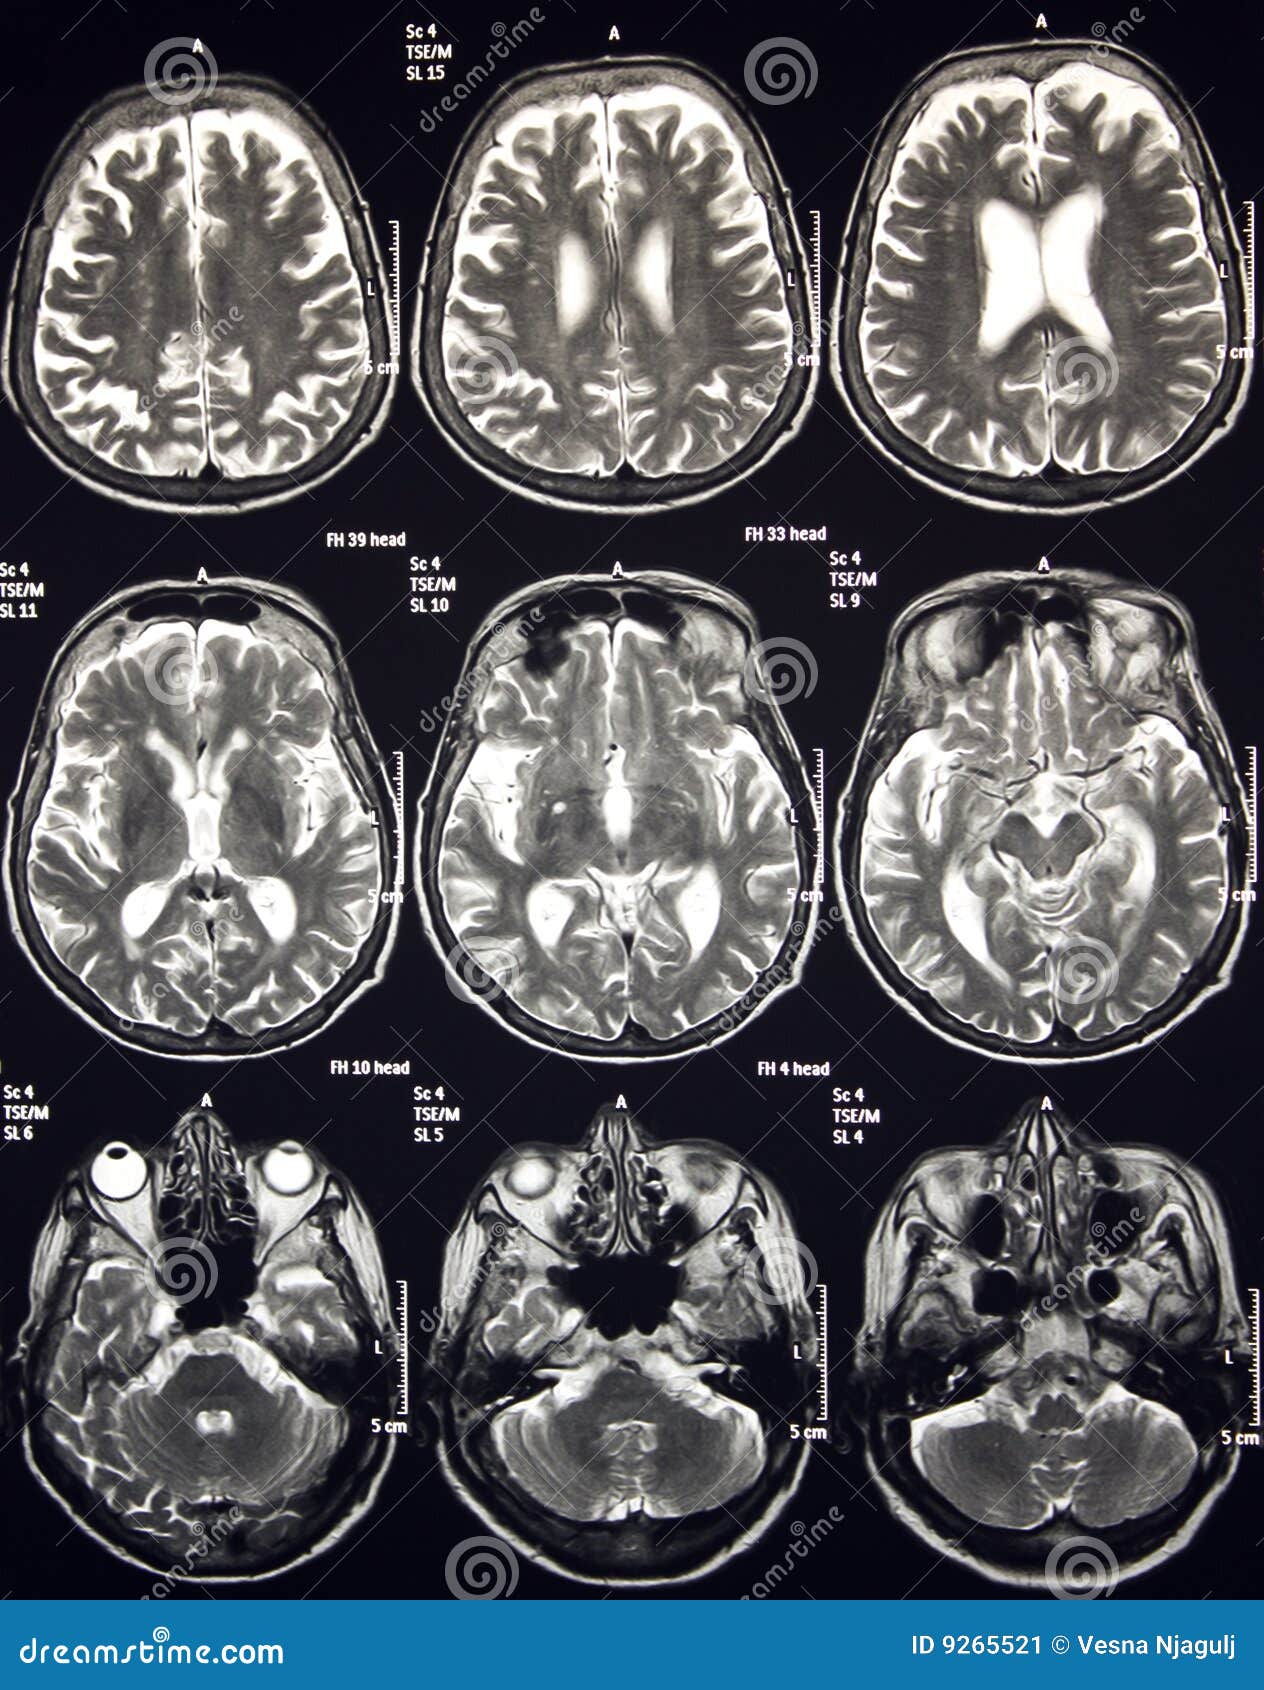

Lista muestra hermosas imágenes de resonancia magnética cerebral normal y anormal dinosenglish.edu.vn para que puedas explorar más en detalle.

resonancia magnética cerebral normal y anormal Pin en NEUROCIENCIAS resonancia magnética de cerebro Resonancia magnética (RM) de cerebro, corte axial ponderado en T2: la … VIDEO Nueva mancha en la Resonancia

Engineer Team : RESONANCIA MAGNETICA Magnetic Resonance Imaging – Clinical Images Hallazgos por resonancia magnética cerebral de nuestro paciente. M, 21 … Imágenes por resonancia magnética anormales como predictoras de mal … Imágenes por resonancia magnética anormales como predictoras de mal … Lesiones en resonancia magnética (RM) del encéfalo y la médula espinal … Pin en Resonancia Magnética del Encéfalo A) Resonancia magnética cerebral (RMC) mostrando infartos en … Caso 1: Edema cerebral visualizado mediante RM. (A) Secuencia T1 plano … Rascacielos dormir pasta tac y resonancia diferencias retrasar … Pin on Apuntes de Enfermería y T.C.A.E Resonancia magnética cerebral secuencia T2, que muestra lesión … Meningitis aguda en la enfermedad de Behçet | Reumatología Clínica Resonancia magnética coronal normal del cerebro Fotografía de stock – Alamy Imágenes de resonancia magnética, la imagen de la cabeza en diferentes … Resonancia magnética cerebral A) protocolo T1 sagital (Caso 1). Se … Resonancia magnética cerebral. Secuencia T1 corte sagital. Atrofia … Resonancia magnética de cerebro, cortes axiales, secuencias T2. Señal … Resonancia magnética de cráneo. A y B) Cortes axiales FLAIR … Resonancia magnética (RM) de cerebro, corte axial ponderado en T2: la … RM cerebral: Interpretación paso a paso | Kenhub Resonancia magnética de cerebro, cortes axiales, secuencias T2. Señal … De Resonancia Magnética De Cerebro Foto de archivo – Imagen de arteria … Top 107+ Imagenes de resonancia cerebral normal – Destinomexico.mx -Imagen por resonancia magnética del cerebro. a) Cortes sagital y axial … resonanCia magnétiCa Cerebral donde se observa hiperintensidad a nivel … MRI (Imagen de resonancia magnética) – Tomografía computarizada de la … Meningioma – NCI Imágenes por resonancia magnética coloreadas del cerebro sano del … Resonancia magnética cerebral en secuencia FLAIR, que muestra lesiones … Contraste resonancia magnetica cerebral – senturinthegreen Relación de los espacios de Virchow-Robin con la enfermedad de … Gliomatosis cerebral – Instituto Nacional del Cáncer Pin en Neurology. Recomendaciones para la utilización e interpretación de los estudios de … Fotografía De La Proyección De Imagen De Resonancia Magnética Del … atmósfera Dirigir Cumplir anatomia resonancia magnetica Desarrollar … Pin en #MEDICINA,#SALUD Resonancia magnética de la nasofaringe De Resonancia Magnética De Cerebro Foto de archivo – Imagen de polilla … Atrofia cortical global de predominio parietal en la Resonancia … Resonancia magnética cerebral | Download Scientific Diagram Neuroblog: Resonancia magnética cerebral en la trombosis crónica de … De Resonancia Magnética De Cerebro Imagen de archivo – Imagen de … ¿Cuáles son los riesgos de la resonancia magnética? – Integra Salud … Resonancia magnética cerebral al decimocuarto día de ingreso: área … Resonancia magnética. Corte axial mostrando área infartada en el … Resonancia magnética cerebral del paciente AV evidenciando lesiones en … -Ressonância magnética de encéfalo mostrando múltiplas imagens … Resonancia magnética cerebral secuencia FLAIR (Fluid Attenuated … Resonancia magnética cerebral con protocolo de epilepsia, en sección … Resonancia magnética cerebral en corte sagital. Se observa una evidente … Resonancia magnética craneal en la que se evidencian lesiones … Logran visualizar el cerebro a detalle más completo tras una resonancia … Así decide el cerebro la severidad de un castigo De Resonancia Magnética De Cerebro, Imagen de archivo – Imagen de … A) Resonancia magnética cerebral; Secuencia Tof: oclusión de arteria … Un estudio asocia la ansiedad con la aparición rápida del Alzheimer IMÁGENES DE 18 F-PR04.MZ PET FUSIONADA CON RESONANCIA MAGNÉTICA … Imágenes por resonancia magnética anormales como predictoras de mal … Tumores de la región pineal – Instituto Nacional del Cáncer Epilepsia: una historia de voces y fantasmas | Neurología Contribución de las imágenes de resonancia magnética por tensor de … Resonancia magnética secuencia T2 plano coronal de quiste epidermoide … Resonancia Magnética Cerebral del paciente: a. Aumento de… | Download … Resonancia magnética cerebral 2022 Síndrome de hemiconvulsión-hemiplejía-epilepsia. Seguimiento de un caso … Enfoque Radiologico: La resonancia magnética permite detectar lesiones … Resonancia magnética craneal T1 con contraste que muestra angiomatosis … guidewiz – Blog Resonancia magnética cerebral, secuencia SWI. Ribete hipointenso en la … resonAnCiA mAgnétiCA de ColumnA Con gAdolinio. Corte sAgitAl en t1 de … SEMANA 12: FUNDAMENTOS DE RESONANCIA MAGNÉTICA NUCLEAR. INDICACIONES Y … DIAGNÓSTICO DE ESCLEROSIS MÚLTIP Magnetic resonance imaging of the brain – Alchetron, the free social … Resonancia magnética de órbitas | Instituto Radiológico Dr. E Castillo Alteración de la marcha en un paciente post-trasplante hepático Resonancia magnética cerebral de un paciente sano (Ay B) y paciente que … Utilidad de la resonancia magnética craneal para el diagnóstico de la … Resonancia Magnética Del Cerebro El Tumor Cerebral Foto de stock y más … De Resonancia Magnética De Cerebro Imagen de archivo – Imagen de … ABDALLA RADIOLOGIA: NEURINOMA ACUSTICO Atrofia cortical global de predominio parietal en la Resonancia … Resonancia Magnética : Producción de la imagen MRI Brain Scan — Stock Photo © Bunyos30 #18724051 Mri (imagen de resonancia magnética) Monitor con imagen de captura de … Tomografía computarizada vs resonancia magnética: diferencia y … Tumores Cerebrales – Unidad de Neurocirugía RGS Resonancia magnética de la columna, sección sagital. Observe los discos … La resonancia magnética, una técnica imprescindible en el diagnóstico … Perfusión Cerebral por Resonancia Magnética | ¿Qué es? ¿Necesita Contraste? Resonancia Magnética Cerebro A: resonancia magnética, T2 coronal preoperatoria; se observa lesión en … Resonancia magnética cerebral — Foto de stock © Bunyos30 #27340623 La resonancia magnética se perfila como detector de mentiras | Futuro … Resonancia magnética cerebral en T1 con gadolinio, cortes axial (a … MRI brain : show brain tumor at right parietal lobe of cerebrum — Stock … NEUROIMÁGENES EN ENFERMEDAD DE PARKINSON: ROL DE LA RESONANCIA …